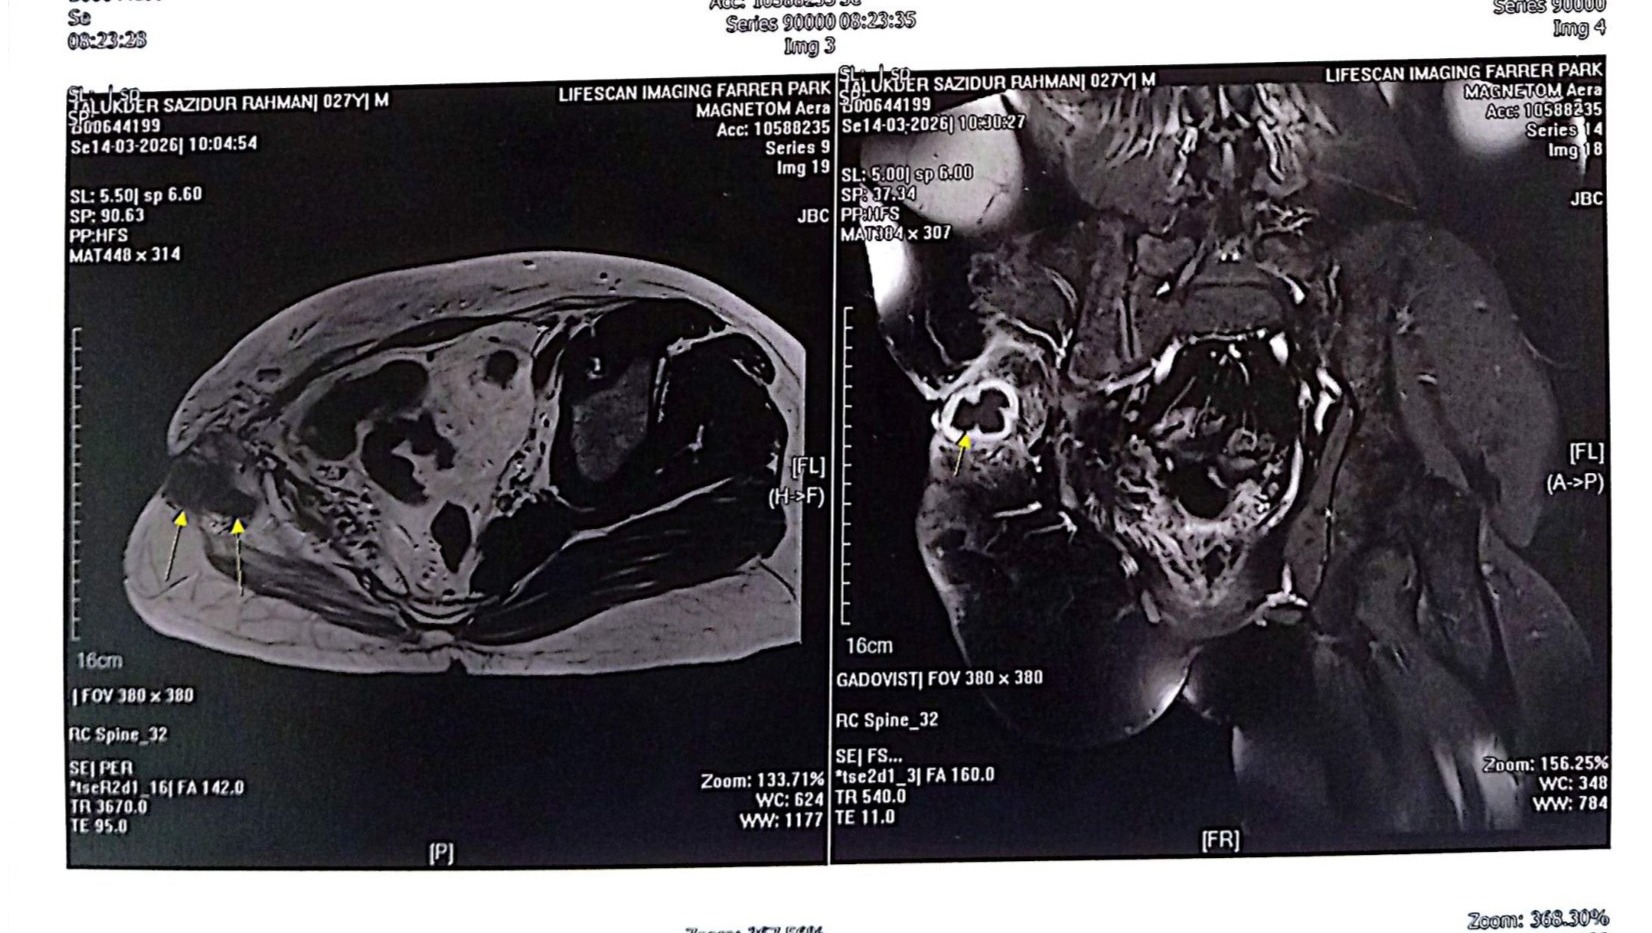

Current Update: A few weeks ago, a new growth was detected near his operated area. After further tests, scans, and a biopsy in Singapore, doctors confirmed that:

1. The new growth contains osteosarcoma cells

2. The cancer has metastasized to his lungs, with multiple nodules detected

He has now been diagnosed with bone cancer (osteosarcoma).

Documents containing recent medical reports, cost receipts, and estimates from his family has also been shared for transparency.

Medical documents and cost receipts: https://drive.google.com/drive/folders/12QXPio8wp-0UFUSakWKIyDq47IlPlF9D?usp=drive_link